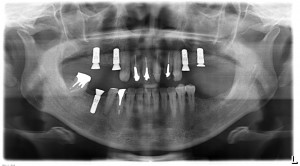

術前のプランニングCT画像です。

術後のレントゲンです。